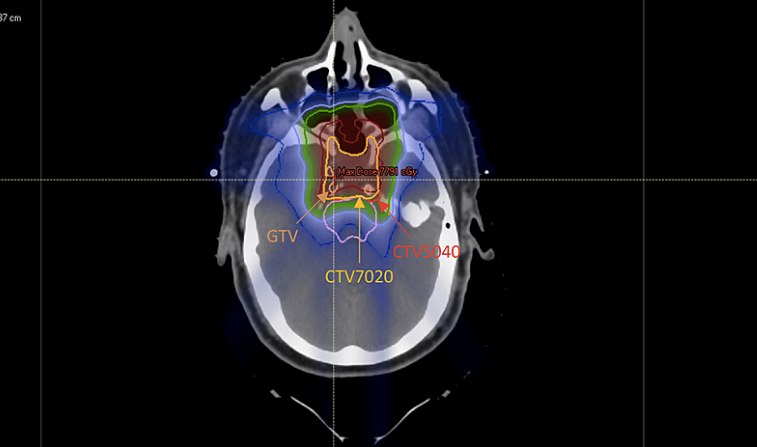

▲质子治疗颅底脊索瘤计量图,图源:参考来源[3]

2021年发布的一项针对质子治疗脊索瘤的研究,纳入了10例颅底脊索瘤患者,研究结果显示,质子治疗脊索瘤的局部控制率和总生存率为100%[3]。